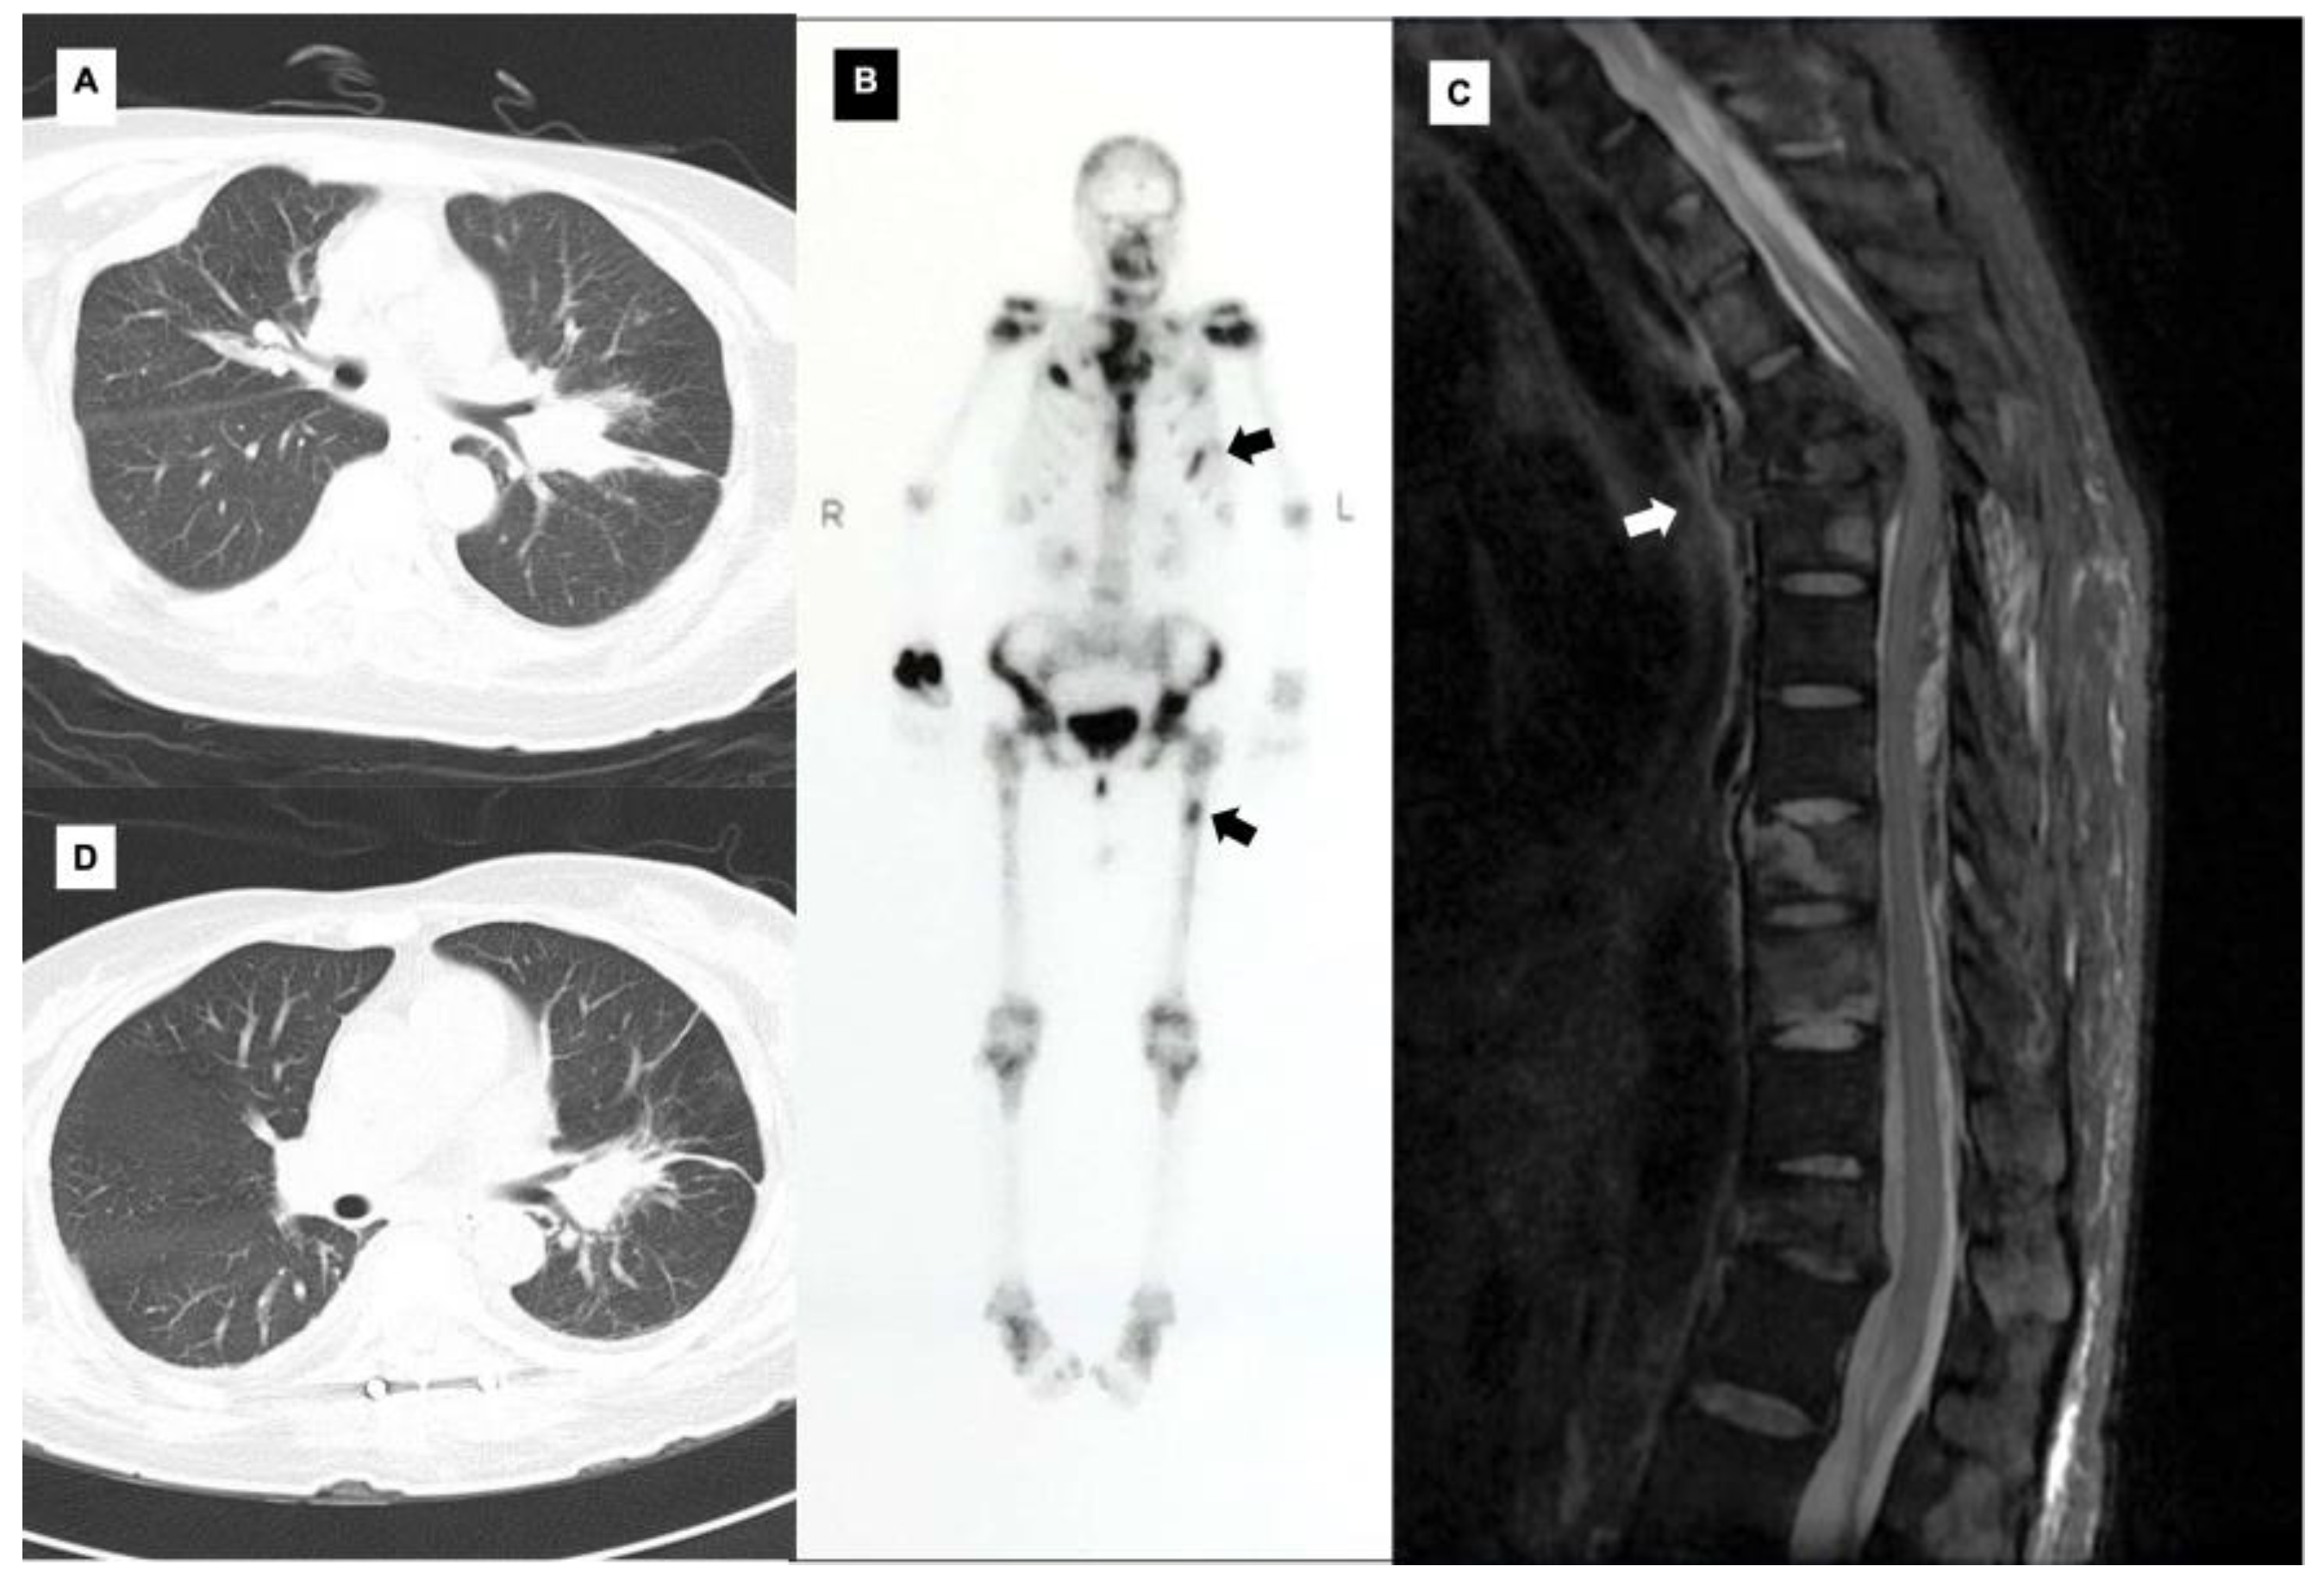

Multiple Bone Destruction Secondary to Mycobacterium kansasii Pulmonary Disease: A Case Report